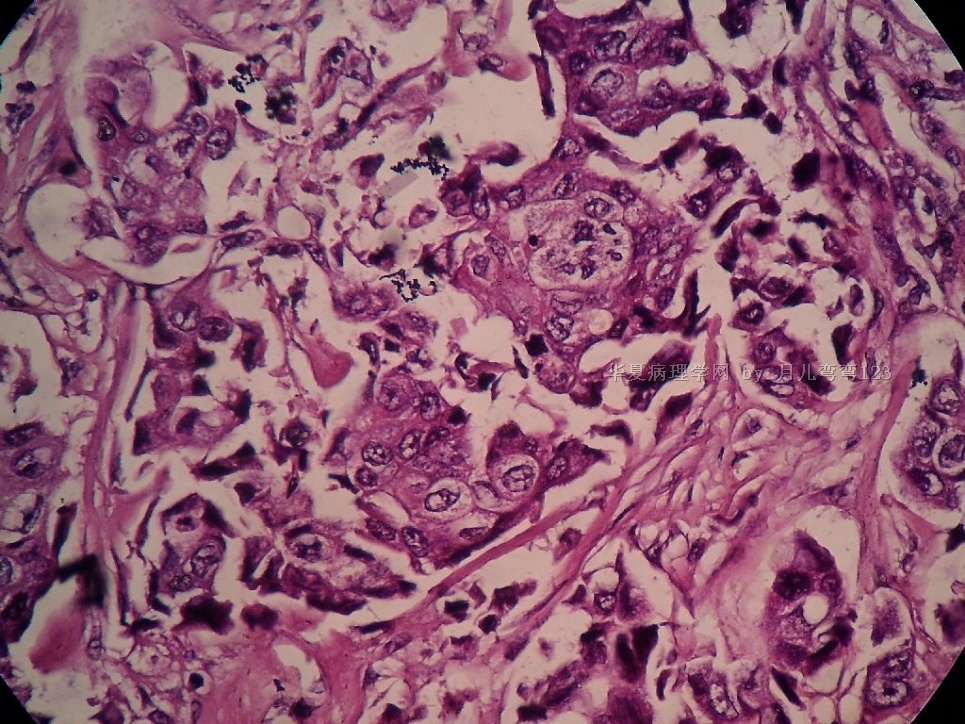

B2778浸润性导管癌?

姓    名: ××× 性别:  女 年龄:  45

标本名称:  左侧近乳晕处肿物

简要病史:  患者描述有疼痛

肉眼检查:  肿物一个2.5*2*1厘米,切面灰白质地硬。

• 浸润性导管癌?图1

• 浸润性导管癌?图4

图4

上皮样细胞,大部分粘附成团成巢,明显浸润。大部分细胞大,核级别高,少数图中见松散的小细胞。未见原位癌。

大细胞考虑浸润性导管癌(3级),小细胞要排除小叶癌。如果有条件请做免疫组化。

分化差的浸润性导管癌